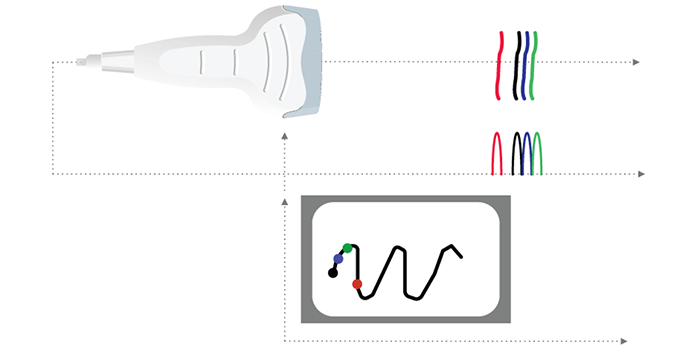

A-Mode

Different ultrasound modes are used in medical imaging today. The A-Mode, or Amplitude Modulation, was the first discovered mode. It is the display of amplitude spikes of different heights, where it consists of an X and Y axes. The X-axis represents the depth, while the Y-axis represents the Amplitude. This image shows an example of the A-Mode display.

The A-mode is mainly used for ophthalmology studies, to detect findings in the optic nerve. Delays are used to determine the depth of an organ, or otherwise to estimate the dimensions of an organ.

B-Mode

The B-Mode, or Brightness Modulation, is the most common form of ultrasound imaging. It is the display of a 2D map of B-Mode data. The B-Mode is based on the brightness which depends on the intensity of the returning echo. In the B-Mode, there is a Z-axis, which represents the echo intensity or amplitude in function of the depth. The B-Mode will display an image of large and small dots, representing strong and weak echoes respectively.

The amplitude of the echo modulates the gray level of a video monitor. This mode allows the representation of ultrasound data collected in a 2-dimensional image.

Therefore, the solid areas will appear in white, whereas the fluid ones in black.

Examples of Images: The gray levels reflect variations in the texture of the internal organs as shown in these 4 different clinical images.

M-Mode

The M-Mode, or Motion Mode, is used to analyze moving body parts, and commonly used in cardiac and fetal cardiac imaging. It is based on the principle of recording the amplitude and rate of motion in real-time, by continually measuring the distance of the object from the single transducer at a given moment. The single sound beam is transmitted, and the reflected echoes are displayed as dots of varying intensities, thus creating lines across the screen.

The M-Mode (Motion Mode) is and commonly used in cardiography, where the direction of the beam is fixed and the returned echoes are recorded as a function of time.

Previously, we mentioned that the M-Mode is a unidirectional examination mode, that allows the analysis of tissue movement. This mode of representation is obtained by scrolling successive ultrasound signals corresponding to the same direction of the beam on a video monitor. The amplitude of the signal is coded in gray level, and useful in echocardiography for the analysis of heart valve movements.